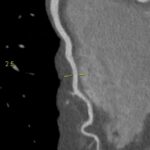

Figururile 1-9: reconstrucție în axul lung al vasului pentru arterele coronare cu evidențierea unui calibru global crescut la nivelul acestora și cu încărcătură ușoară-moderată de placă în principal calcificată

Discuţie caz nr 132: Examinările coroCT se efectuează în principal pentru aprecierea încărcăturii de placă precum și pentru evidențierea reducerilor de lumen ce necesită tratament. Această examinare a evidențiat creștere globală a calibrului arterelor coronare și o încărcătură ușoară-moderată cu placă în principal calcificată, fără a se evidenția arii de stenoză.